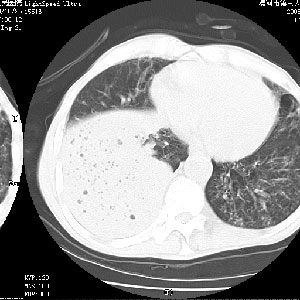

叶间裂前移,能考虑肺不张和肺栓塞吗?为什么不增强?大叶肺炎不能考虑吗?

坠积性肺炎合并右下肺膨胀不全

右肺下叶肺脓肿,右肺下叶支气管痰栓形成。

考虑右肺下叶脓肿,右肺下叶支气管痰栓。